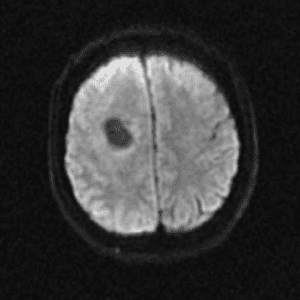

Case #2

Cavernous malformation